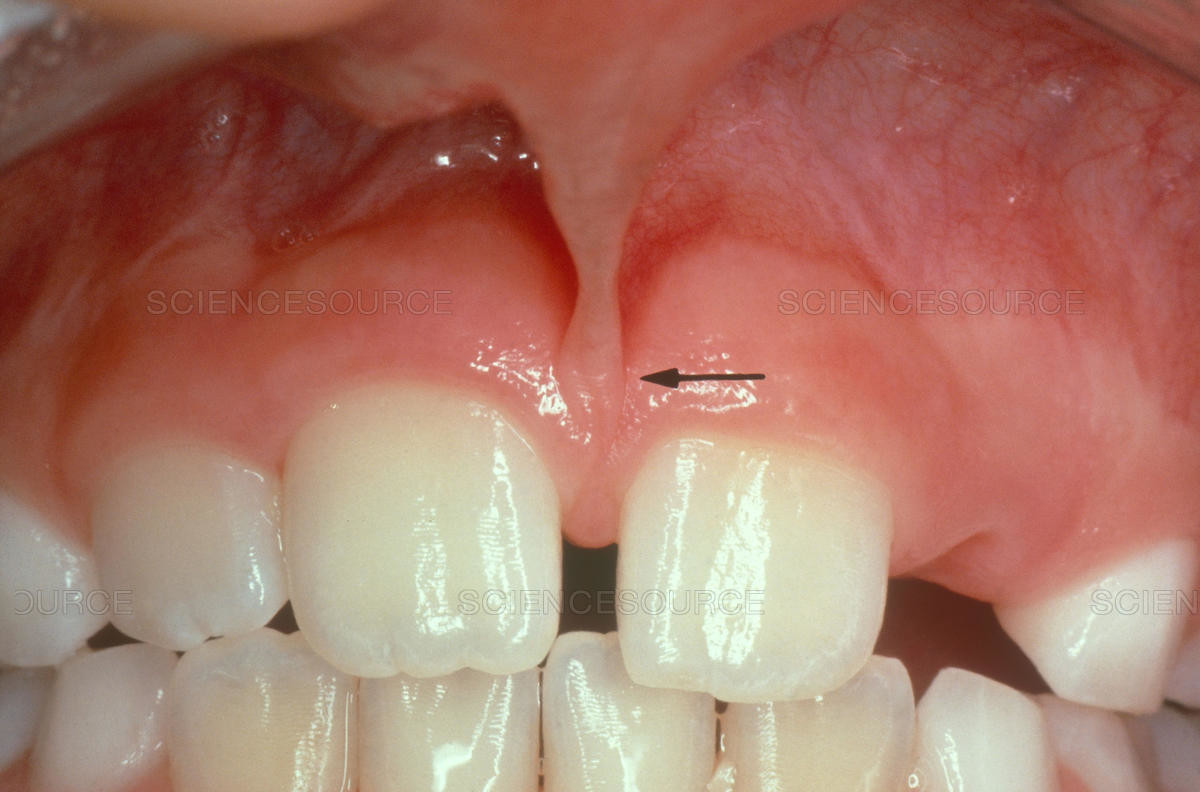

Frenulum In The Mouth

What Is A Frenum (Frenulum)?

In our mouth, most people have two groups of tissue called frenums found in and around the gums and teeth. It is a piece of really soft tissue that appears as a thin line between the gums and lips. You can find it on the top and the bottom of your oral cavity. There’s also a frenum that extends along the bottom of the tongue and connects to the bottom of the mouth just behind the teeth. Different people have different frenums. It can vary in length and thickness.

Types Of Frenum

There are two basic types of frenums in your mouth:

Labial frenum – This type of frenum is placed in the front of your mouth between the upper lip and gum. His counterpart is positioned between the lower gum and the lower lip. If there is an issue with this type of frenum, it can change the way your teeth grow in and can influence your dental health. Particularly it can pull your gums away from a tooth revealing the root.

Lingual frenum – This type of frenum is located between the floor of your mouth and the base of your tongue. It comes in different sizes and sometimes it can limit the movement of your tongue. This means frenum is tight, and we call this condition: tongue-tie. If this happens, it can affect the way the tongue moves in your mouth. This problem is especially annoying for babies because it makes it hard for a baby to feed properly.

Possible Problems With Frenum

The main purpose of a frenum is to give the lower and upper lip, as well as the tongue proper support and more stability in your mouth. If you suffer from an oversized frenum, it can lead to various problems that can affect your teeth, gums, and mouth.

Some of the conditions you may encounter if there’s an issue with a frenum include:

· disruption of the healthy growth of your upper two front teeth, which may cause a gap

· the gap formed between front teeth

· receding of gum tissue away from the root of the teeth and revealing the tooth root.